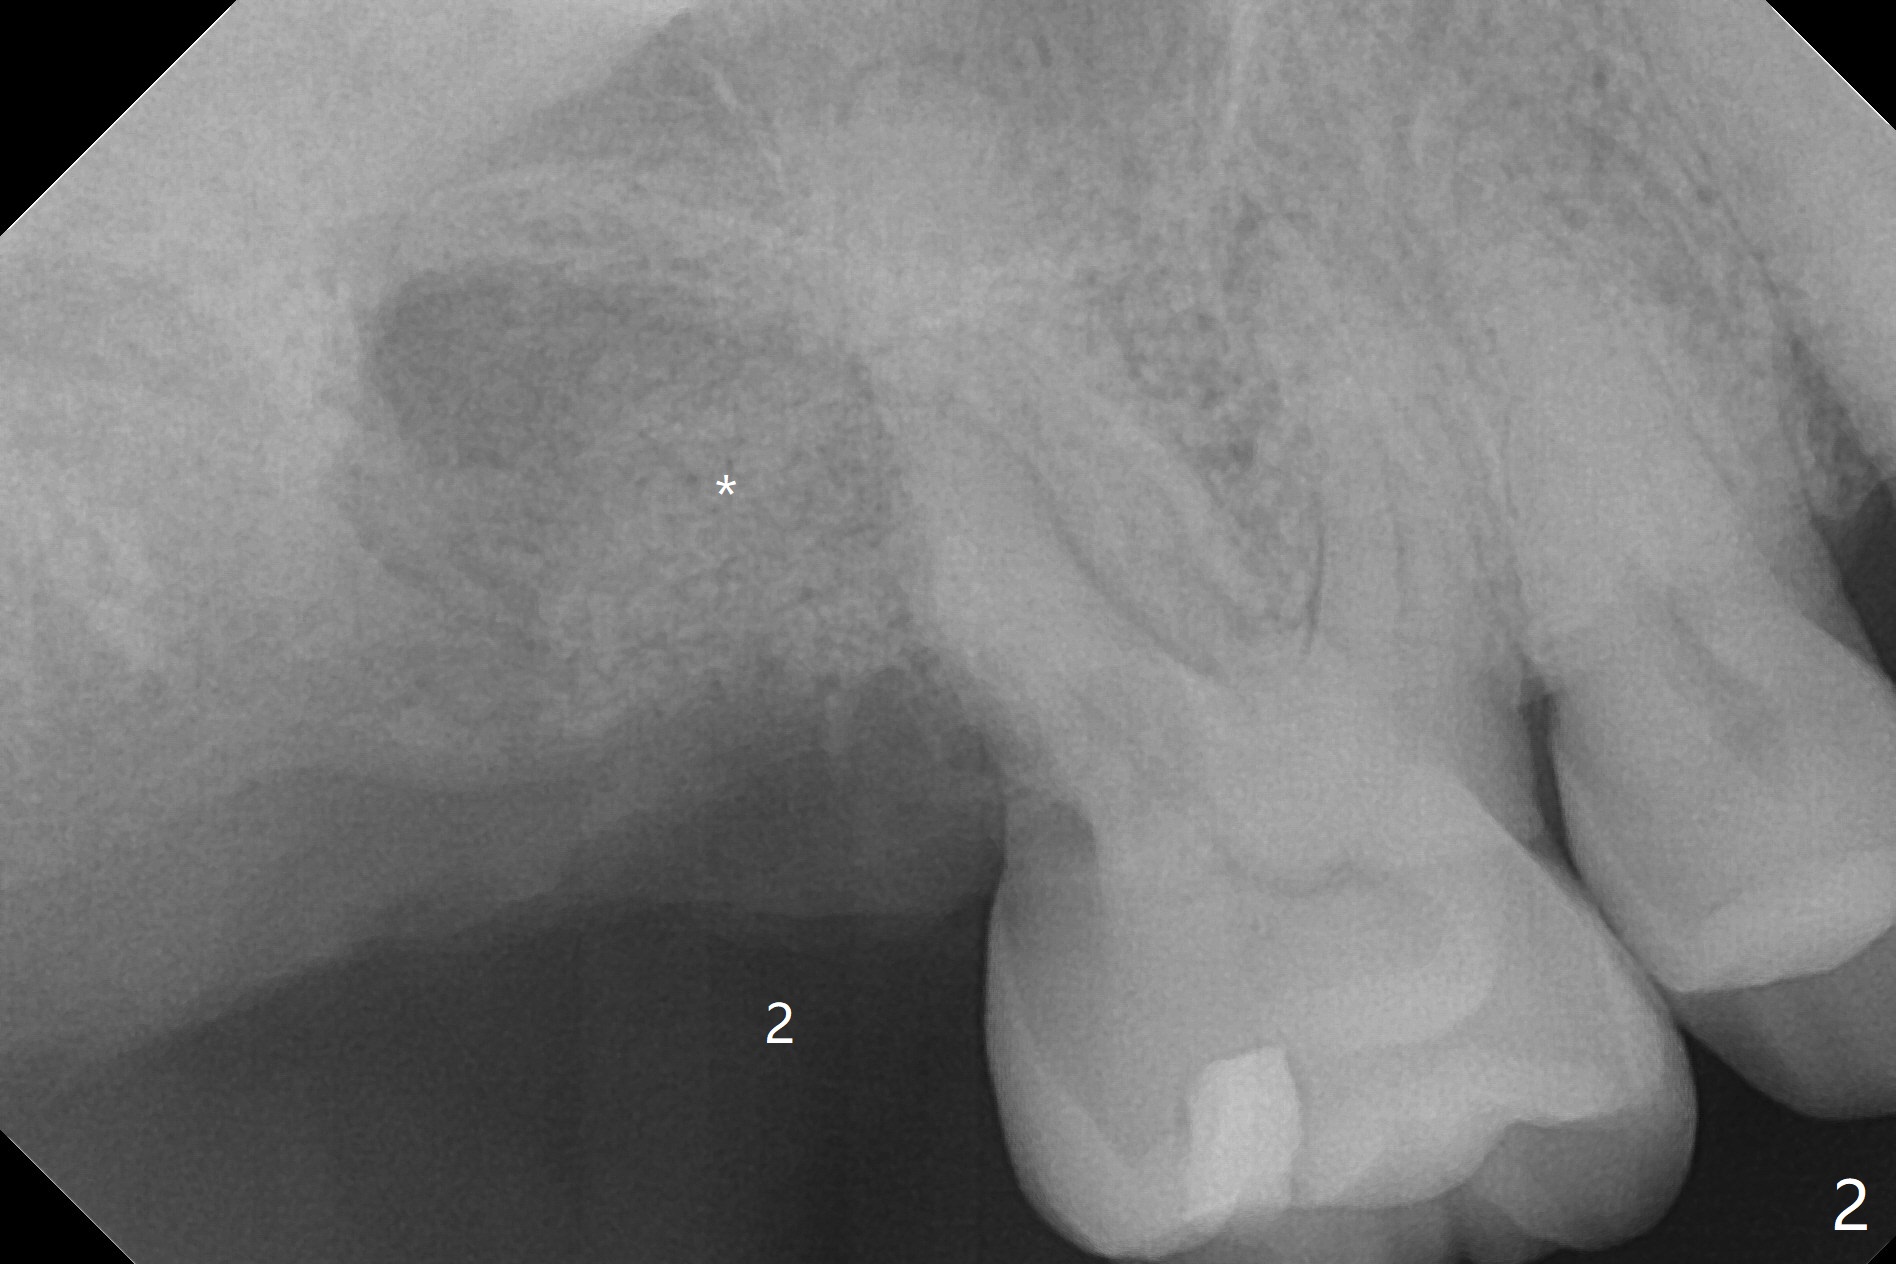

A 55-year-old man agrees to have the tooth #1 extraction immediately post SRP. Pre-extraction panoramic X-ray shows severe bone loss at #2 (Fig.1). Possible extraction of #2 is mentioned considering pending implant at #14. Extraction of #1 turns out to be difficult, requiring sectioning. The tooth #2 blocks the access. The patient readily accepts #2 extraction. Removal of abundant granulation tissue at #2 is associated with severe hemorrhage from the Greater Palatine Vessels. After pressure hemostasis, a piece of Osteogen Plug is placed at #1, the other palatal of #2 to control hemorrhage. With hemostasis, Vanilla graft is placed at #2 securely (without being washed out, Fig.2 *), followed by placement of a third Osteogen Plug on the top of the graft. The last surgical challenge is to close these two large wide sockets with 4-0 Chromic gut and PGA. While the socket #1 remains closed, the one at #2 is open 13 days postop (Fig.3). It appears that a stiffer membrane (6-month) should be sutured in place to keep the Osteogen plug underneath in place. The latter seems to be easily fragmented.